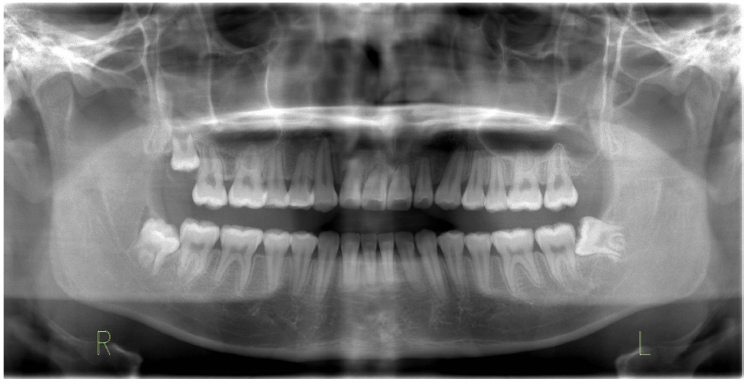

The treatment objectives were to expand the maxillary arch, coordinate arches, eliminate the posterior crossbite, and establish a Class I molar and canine relationship. Treatment was started by bonding metal 0.022-in slot pre-adjusted edgewise appliances with a rapid palatal expander (RPE) to correct the posterior crossbite. Instruction was given to the patient and parents to do one turn per day of the expansion screw for 14 days. The RPE was removed after a five-month retention phase. A pendulum appliance was then delivered to start the distalization process. After eight months, enough space was created for both maxillary canines, and a Class I molar relationship was achieved (Figs. 5 and 6). Detailing was performed using 0.017 x 0.025 titanium molybdenum alloy (TMA) archwire. Upon completion of treatment, maxillary and mandibular Hawley retainers were delivered, and the patient was instructed to wear the retainer for 24 hours per day (Figs. 7 and 8).

The patient’s chief complaint was addressed. Acceptable esthetic and functional results were achieved. The crowding in the maxillary arch and spacing in the mandibular arch were eliminated, and transverse discrepancies were corrected.